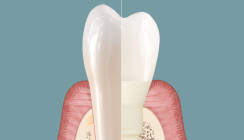

Die mukosale Schutzbarriere schirmt das Gewebe vor Plaquemigration und Bakterien ab (Abb. 2). Dadurch können Behandler die für Zahnimplantate typischen Nebenwirkungen (43% Mukositis und 22% Periimplantitis6) deutlich reduzieren respektive gänzlich vermeiden.1, 2

| Abb. 1: Rasterelektronenmikroskopische Aufnahme zeigt das Verwachsen von Weichgewebe mit Patent™ Symbionic Teeth (© Dr. Roland Glauser). | Abb. 2: Histologischer Querschnitt zeigt den Verbund zwischen Saumepithel (JE) und Patent™ Oberfläche, welcher die Migration von Plaque und Zahnstein (CAC) in die Gewebe verhindert (© Dr. Peter Schüpbach). |